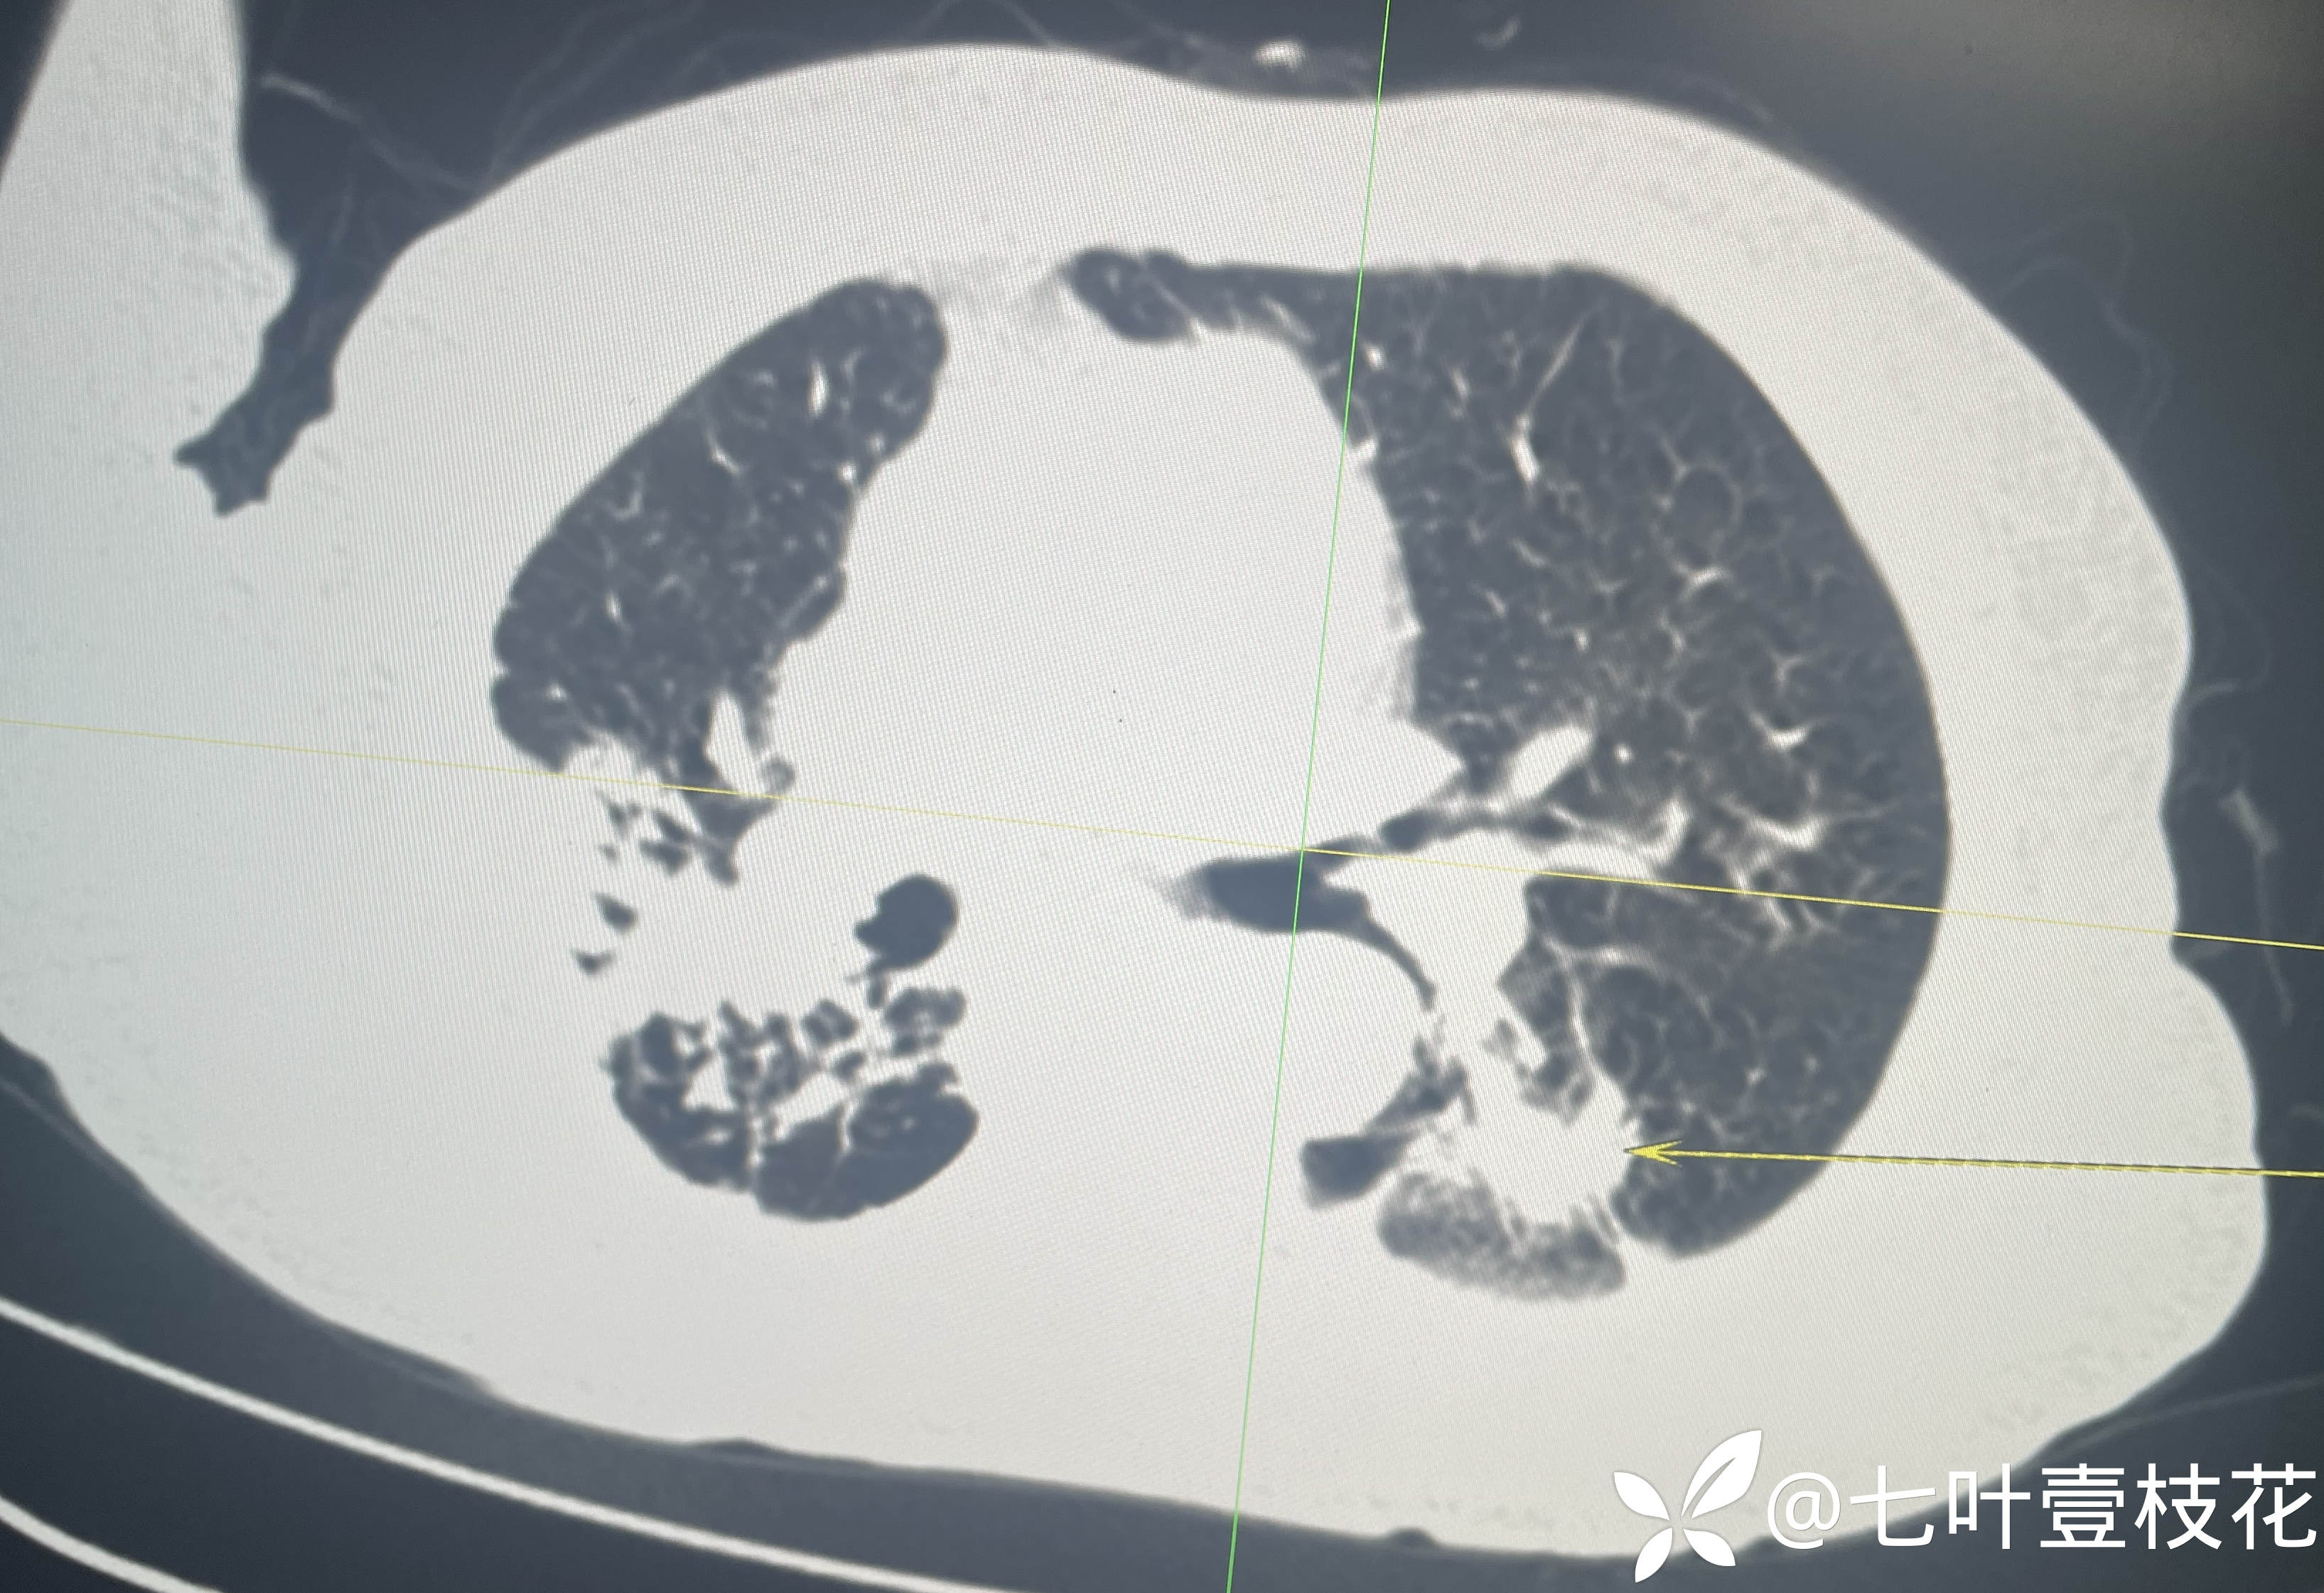

8月5日,入院第一天全腹CT

下面是腹主动脉CTA动态视频(动脉期和静脉期)及文字报告:

8月7日,入院第三天腹主动脉CTA

这位患者是8月5日凌晨入院的,第二天完善了肠镜,经治疗后到8月6日未再便血,腹痛也有所缓解,8月7日出现解黄色稀水样便3次,每次约100-200ml,其内可见少许类似肠道组织样絮状物,腹痛加剧,后来完善腹主动脉CTA后转上级医院进一步治疗了。病检目前未回,上级医院检查结果后续随访补充。